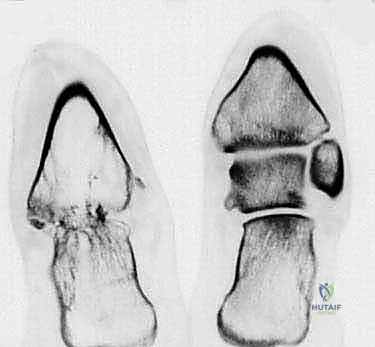

Acute talar bone loss and subsequent AVN and infection will present a cascade of hindfoot reconstruction problems (FIG 1).

FIG 1 • The extent of bone loss and infection will determine the reconstruction. A. Extensive infection of the talar dome compromising tibial talar arthrodesis. B. Complete necrosis of the talar body. C. Necrosis of the entire talus. D. Necrosis of the plafond and talus. E. Traumatic ejection or crushing of the talar body. F. Traumatic ejection or crushing of the talus.*

Open fracture-dislocations of the talus are high-energy injuries that cause disruption of the blood supply by dislocation, ejection of fragments, and fracture through the neck of the talus. This causes AVN of the body or entire talus, which is susceptible to infection (see FIG 1).